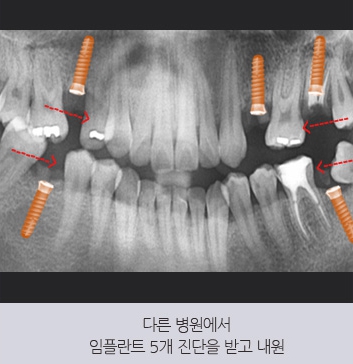

30대 남성 환자분이 다른 치과에서

5개 임플란트를 권유받고 내원하셨습니다.

본원에서는 돌출입을 개선하는

교정 치료를 함께 진행하여

기존 치아를 활용할 수 있도록 유도하였고,

사랑니를 이동시켜

빈 공간을 채우는 방법을 적용하였습니다.

그 결과, 식립 개수를

5개에서 1개로 줄일 수 있었습니다.

또한, 교정 치료를 통해 잇몸뼈의 높이가 올라가

건강한 상태로 회복되었으며,

입술 라인이 개선되어 심미적인 효과까지

함께 얻을 수 있었습니다.